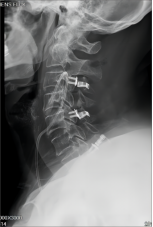

2.颈椎后路减压固定技术

颈椎后路减压技术适用于:脊髓型颈椎病伴发育性或多节段退变性椎管狭窄者;多节段OPLL;颈椎黄韧带肥厚或骨化所致脊髓腹背受压者。有节段性不稳定者可以同时行侧块钛板螺钉或经椎弓根螺钉内固定、植骨融合术。我科在区域内率先开展颈椎单开门、双开门技术,颈椎椎板切除减压椎弓根内固定术,均获得满意疗效。